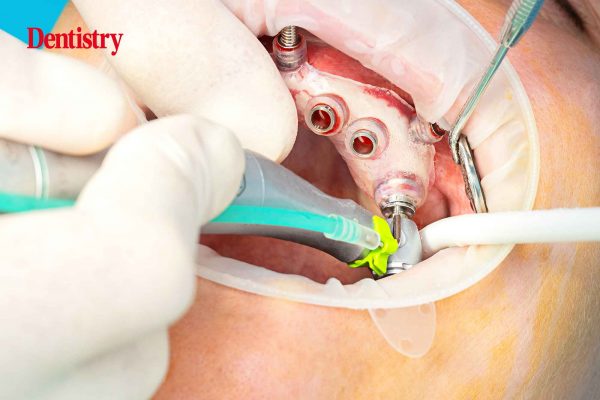

Guided implants = predictable and stress-free placement

Gurs Sehmi shares with readers his experiences performing guided implant placement and offers insight into how to get the best…

Full arch workflow – a systematic approach using Chrome

Ken O’Brien explores how the team at Quoris 3D are changing the face of dentistry with their pioneering Full Arch…